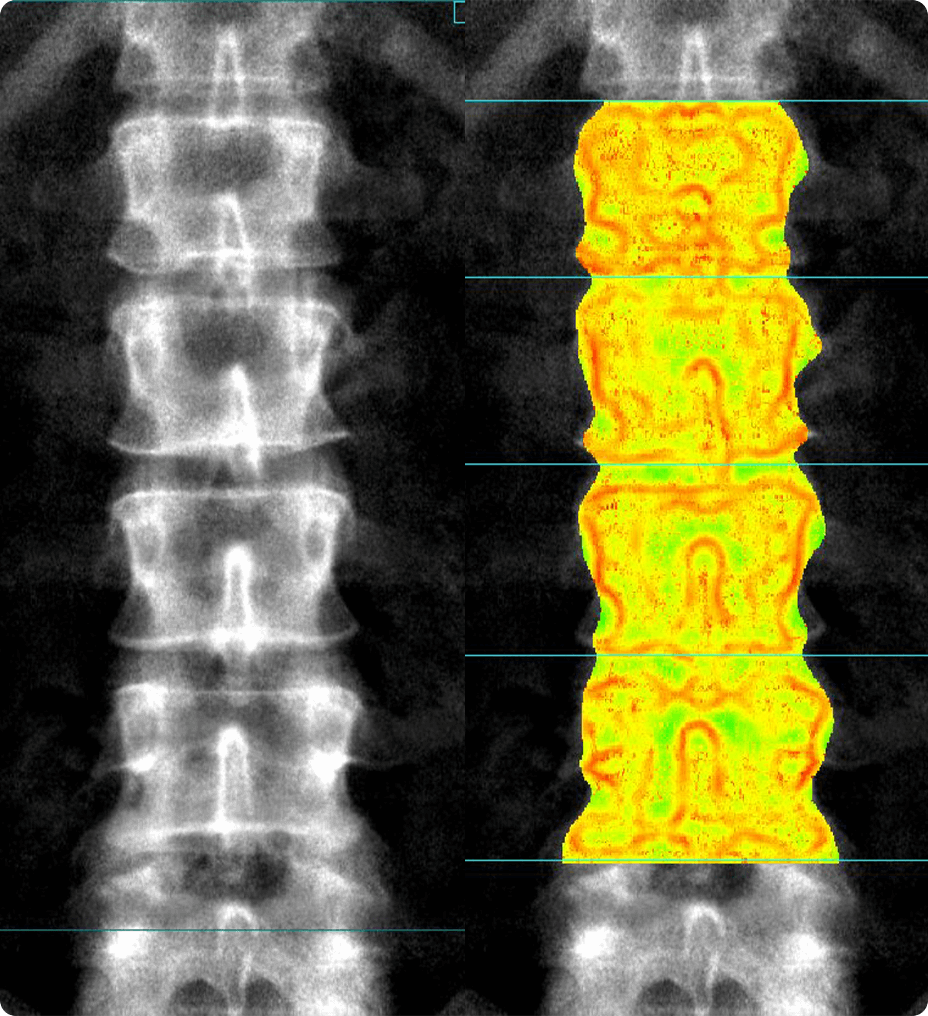

Using ISUOG practice guidelines, SonoLystIR automatically detects recommended views. It identifies anatomy, then selects applicable annotations and measurements. Confirm and data is entered into the Scan Assistant checklist and report, enhancing workflow and reducing variability.